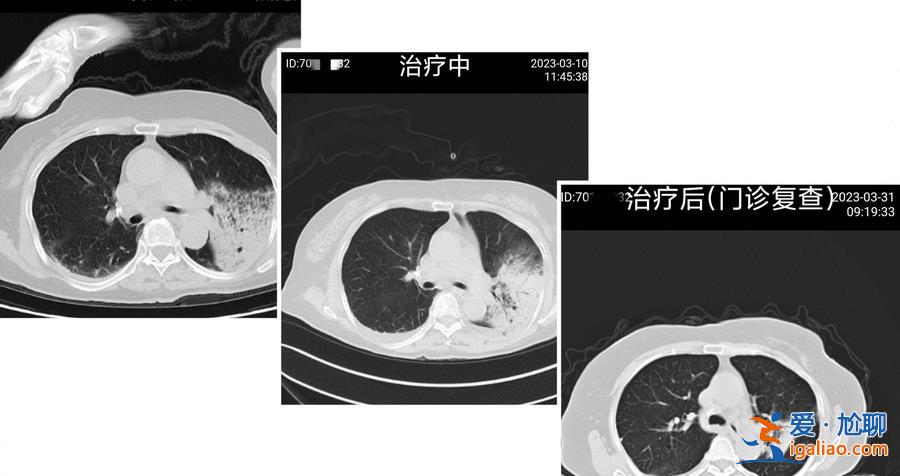

經(jīng)多次仔細(xì)詢問,忻阿婆的家屬提到,她居住的房屋樓頂有人飼養(yǎng)飛禽。醫(yī)生考慮,此次感染或與飛禽飼養(yǎng)相關(guān)。10余天后,忻阿婆的肺部感染好轉(zhuǎn),言語逐漸清晰,對答無礙,能自己吃飯和活動了,很快康復(fù)出院。